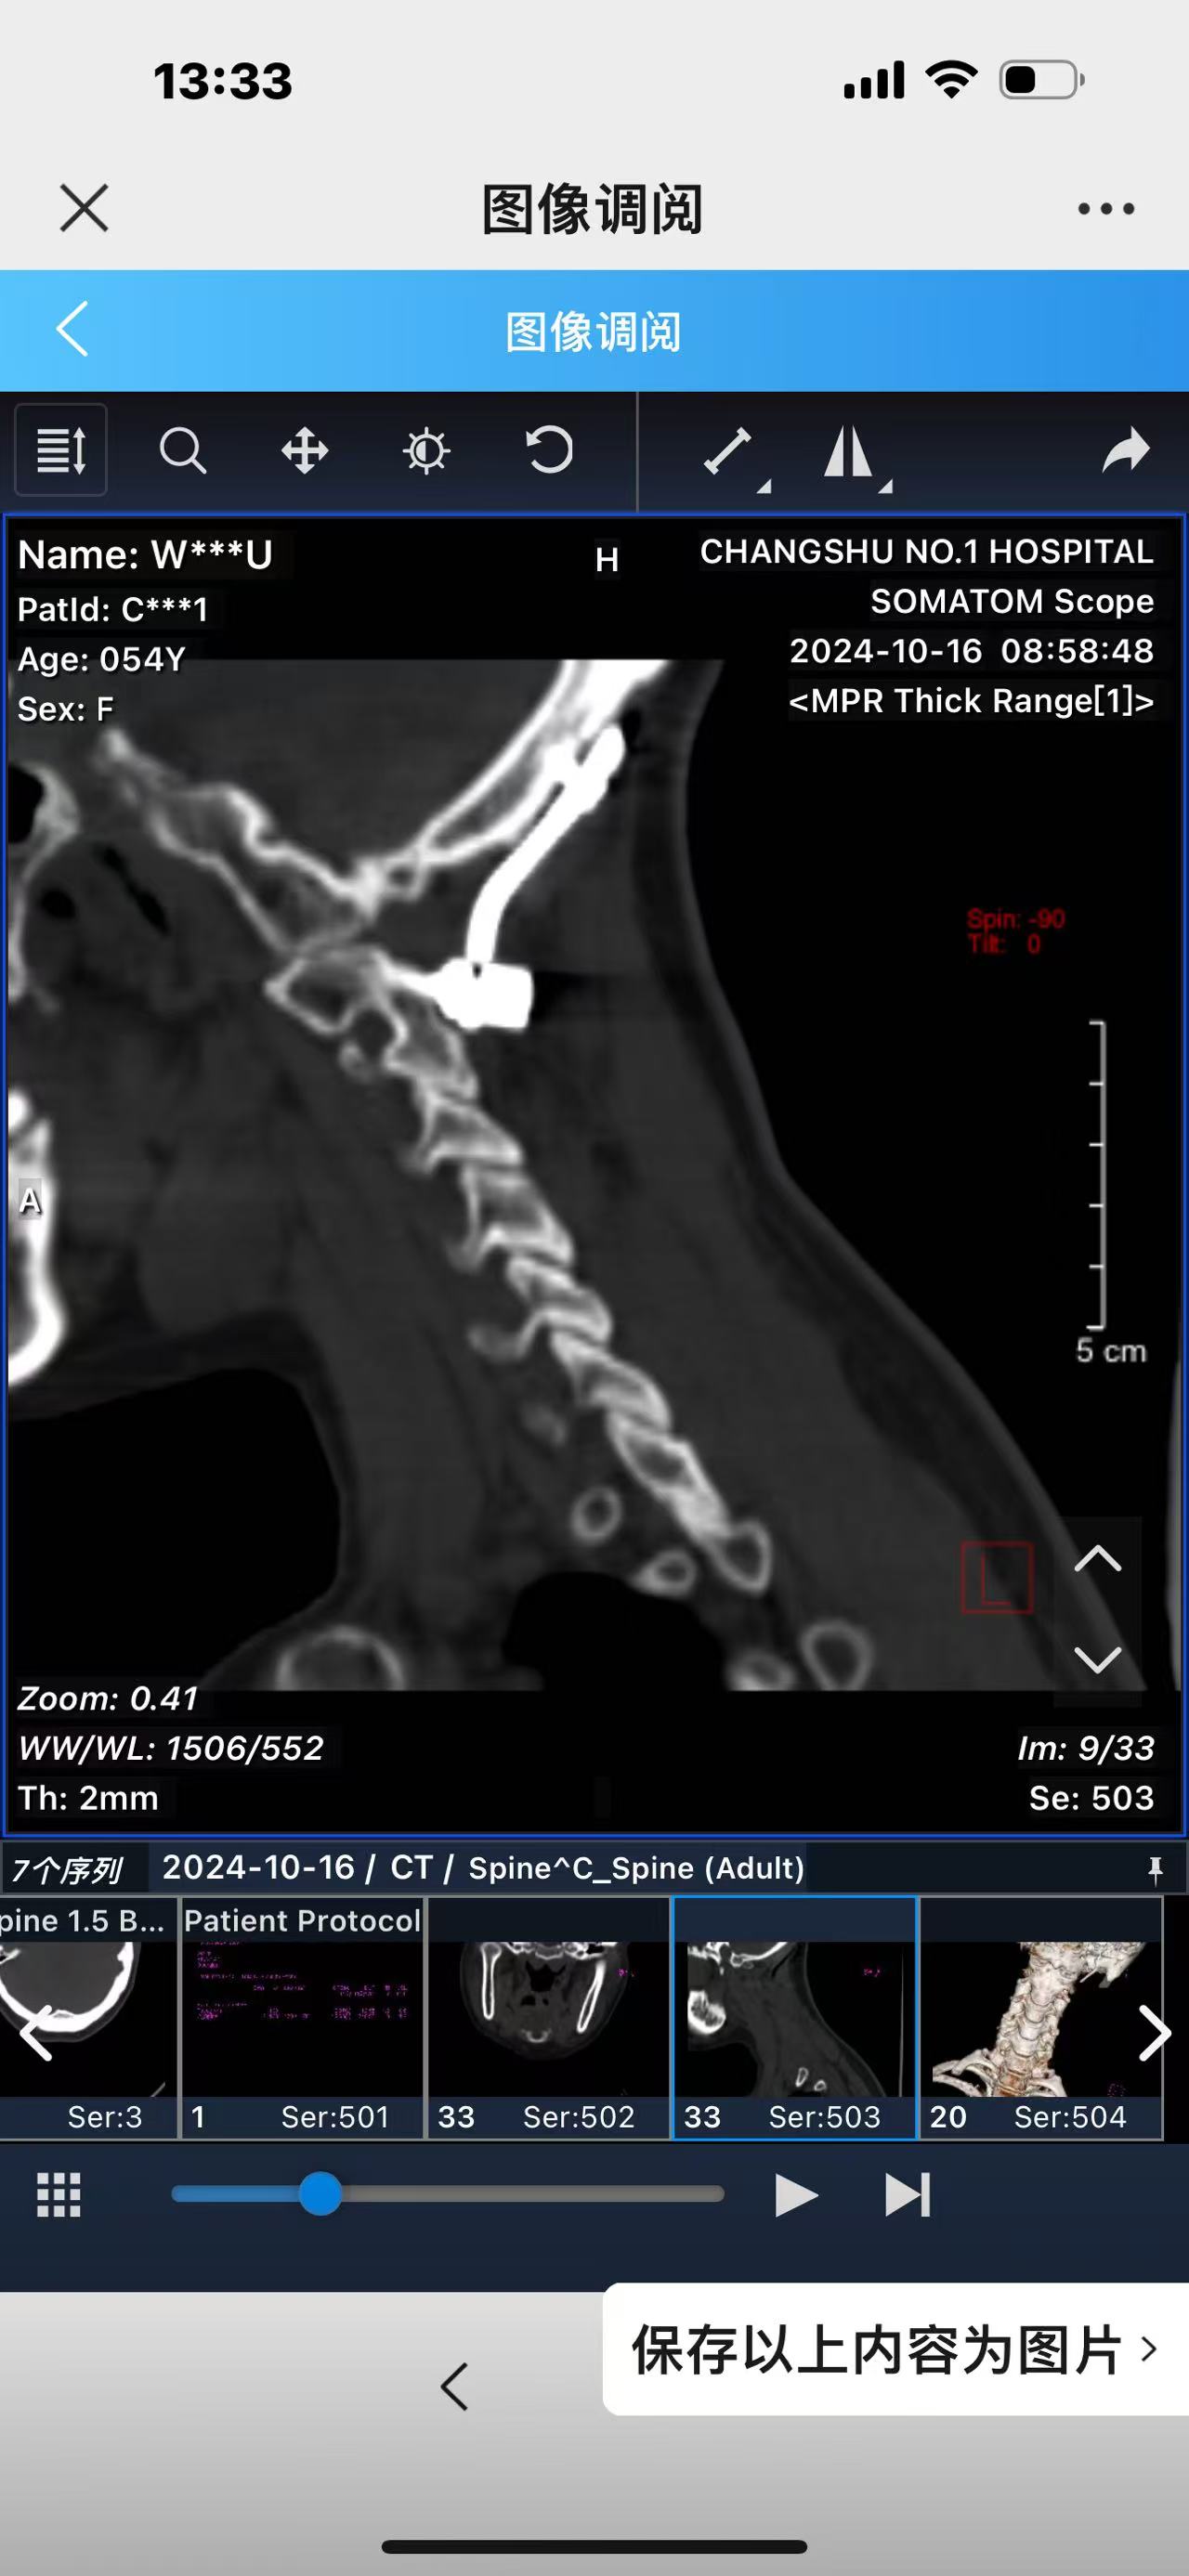

• 诊断:寰枢椎脱位,颅底凹陷

• 术后影像:

• 2024.10.20,复查,对位良好,偶尔会肩甲骨酸,坐下就不酸。